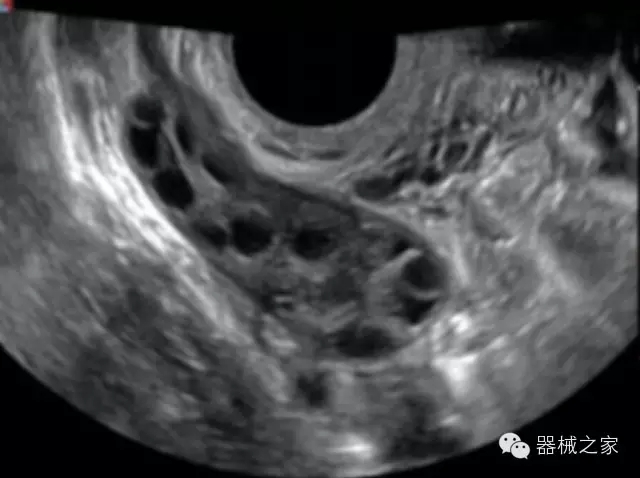

品牌:飛依諾(VINNO)

公司簡介:

飛依諾科技(蘇州)有限公司2010年在蘇州工業(yè)園區(qū)成立,公司致力于成為世界一流醫(yī)療超聲品牌。核心創(chuàng)始團隊囊括了來自于全球著名公司十多位資深研發(fā)和市場人才,均為業(yè)界精英。

官方網(wǎng)站:www.vinno.com

經(jīng)典產(chǎn)品:VINNO 6

臨床圖片賞析

產(chǎn)品特點

·獨有的RF平臺提高微小細節(jié)顯示、圖像對比度和邊界清晰度;

·特有的XCEN探頭,超寬的帶寬,表現(xiàn)更高分辨率和對比度;

·單晶純凈波探頭提供更佳的穿透力和彩色敏感度;

·完整的3D/4D臨床應用,STIC, MCUT 和Auto NT等滿足產(chǎn)科所有應用;

·更高的HQ羊膜腔鏡成像技術精細觀察每一個暗區(qū)細節(jié);